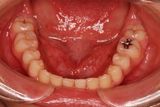

健康な小臼歯を抜いていません

矯正前                 矯正後

治療前 の 上アゴ です 動く矢印治療後 の 上アゴ です

治療前 の 下アゴ です 動く矢印治療後 の 下アゴ です